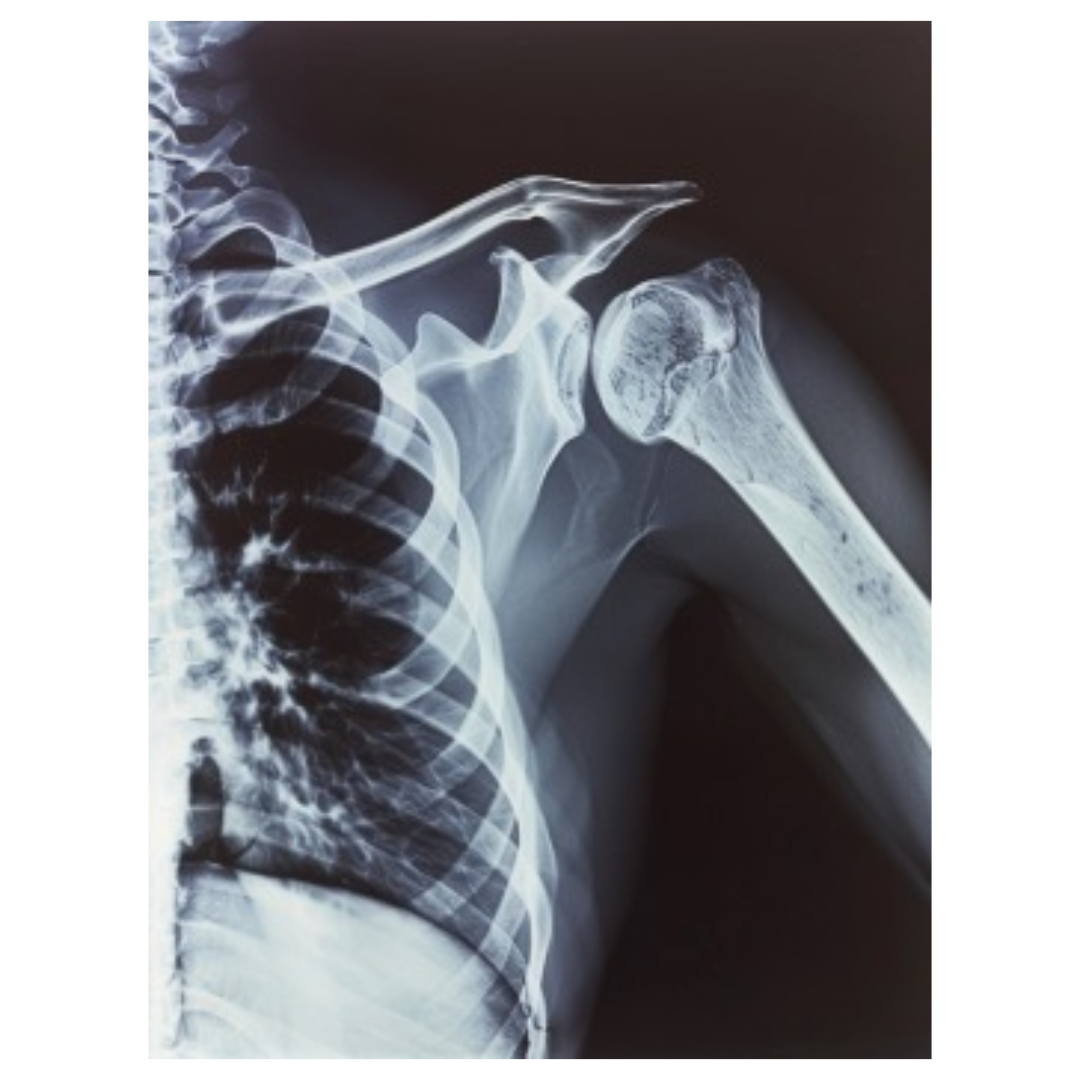

초기에는 작은 관절, 특히 손가락, 발가락 같은 부위에서 시작되지만, 이후에는 손목, 무릎 등 더 큰 관절로 퍼질 수 있습니다.

2. 관절의 변형 시작

손가락이나 발가락 같은 작은 관절에서 시작하여, 뼈가 조금씩 변형되기 시작합니다. 이때 손가락이 약간 휘어지거나, 발가락이 비틀 어지 듯한 변형이 관찰될 수 있습니다.

1. 심각한 관절 변형

손가락, 발가락뿐만 아니라 손목, 무릎 등의 관절에도 변형이 일어납니다. 관절이 휘어지거나 부러지듯 변형되며, 외관상으로도 뚜렷이 보이게 됩니다.